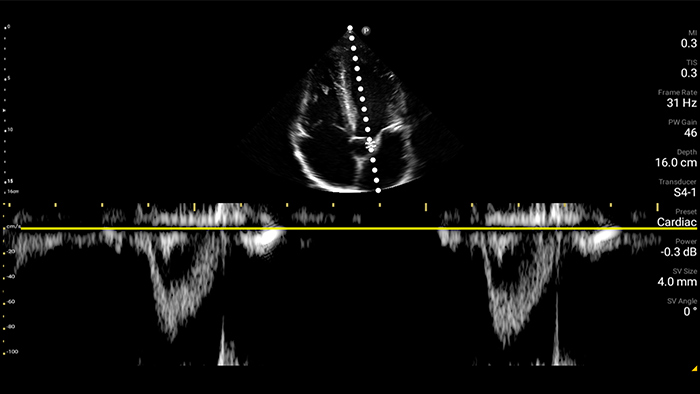

Every second counts in cardiac care

Heart attack patients need immediate care. Lumify's cardiac presets can help patients get diagnosed faster to improve their outcomes.

Lumify S4-1 broadband phased array transducer

• 4 to 1 MHz extended operating frequency range • 2D, color Doppler, M-mode, advanced XRES and multivariate harmonic imaging • High-resolution imaging for abdominal and cardiac applications: Cardiac, OB/GYN, Lung, Abdomen and FAST imaging preset optimizations Lumify aids life-saving technology in prehospital setting